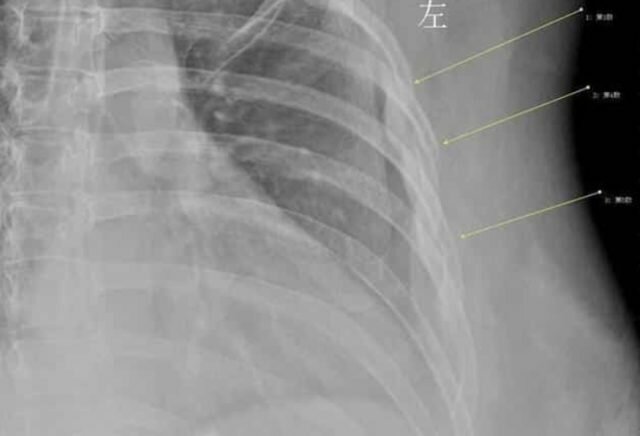

Həkim, ağrının səbəbini tapmaq üçün rentgen istədi və əsl problemi orada gördü. Xanın üçüncü, dördüncü və beşinci qabırğalarının şiddətli öskürək səbəbiylə qırıldığını gördü.

Doktor 30 yaşlı Xana sümük quruluşunun 60 yaşlı bir qadına bərabər olduğunu dedi. Və Xan təəssüf ki, erkən osteoporoz yolundaydı.